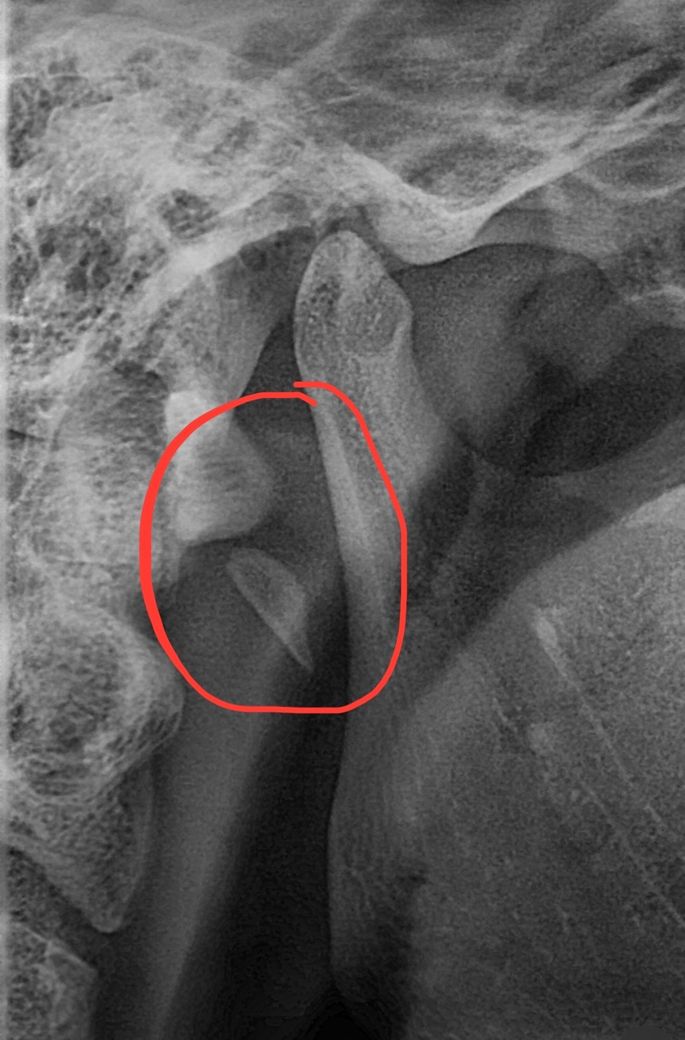

치아 파노라마 영상인데 목뼈 앞으로 뼈조각이 보여요

치아 파노라마 영상입니다.

해당 사진속 목뼈 앞으로 뼛조각 형태의 해부학적 구조가 무엇인지 알고계시는 의사선생님 계실까요?

사진에 보이는 부분의 귀쪽인거 같습니다. 일반적으로 저렇게 단독적으로 떨어져서 보이는 구조물은 없습니다. 아마 사진이 흔들린게 아닐까 생각됩니다.

경추부위의 방사선상에서 불투과상이 나타나는 경우는 병소일 수도 있고 정상 해부학적 구조일 수도 있는데요 다양한 경우의수가 존재하는데요.

해당 부분은 stylohyoid ligament로 보입니다.